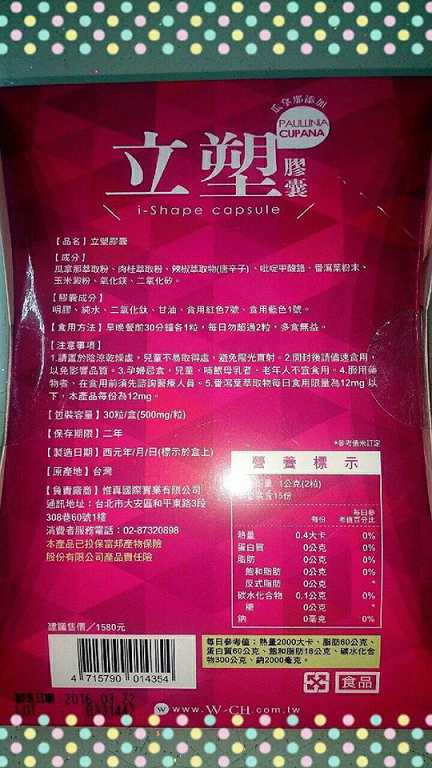

每一盒Supercut塑魔纖立塑膠囊都有三小包,每一小包有10顆膠囊

Supercut塑魔纖立塑膠囊的成分有:瓜拿那萃取粉、肉桂萃取粉、辣椒萃取物(唐辛子)、吡啶甲酸鉻、番瀉葉粉末、玉米澱粉、氧化鎂、二氧化矽。

食用方式:早晚餐前30分鐘各1粒,每日不超過2粒。(多食無益)

番瀉葉萃取物每日食用限量為12mg以下,

鉻與脂肪代謝有關,有助於控制血液中的膽固醇,並有降低血壓的作用,可以預防高血壓,對降低體重也有不錯的效果。

鉻與脂肪代謝有關,有助於控制血液中的膽固醇,並有降低血壓的作用,可以預防高血壓,對降低體重也有不錯的效果。